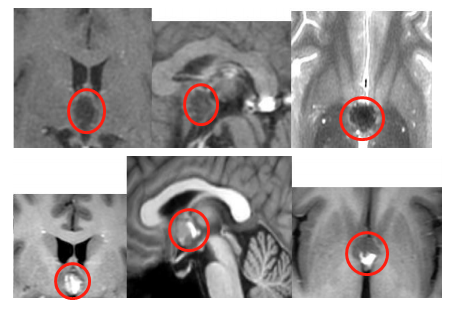

西藏景色美不胜收,但返回后浩然开始频繁出现头痛、头晕症状。起初以为是高原返回后的“醉氧”反应,预计休息数日即可缓解,然而症状持续未好转,甚至在旅行结束两个月后仍然存在。与普通头晕头痛不同,浩然的表现伴有坐下站立时头后部及尾椎部同步疼痛,偶有站立不稳。头颅核磁共振检查提示第三脑室病变,疑似海绵状血管瘤,大小约14x13x10mm。

保守治疗2个月后,浩然的症状未见缓解,反而呈现加重趋势,表现为头昏脑胀、头晕及精神不振。医院核磁复查显示病灶范围较前增大、信号混杂,大小约16x14x14mm。短短2个月内肿瘤进展迅速,症状加重原因考虑为海绵状血管瘤伴出血。海绵状血管瘤一旦出血,再次出血概率将增加,间隔时间缩短,相应症状也会加重。此次医生未建议继续保守治疗,而是推荐手术治疗。

手术过程:采用额底成形开颅术,广泛开放额窦,经大脑纵裂额底入路行显微外科血管畸形全切术。手术顺利实现血管畸形全切,电生理监测下无新发神经损伤,未出现术中及术后并发症。术后第一天转出ICU,返回普通病房。